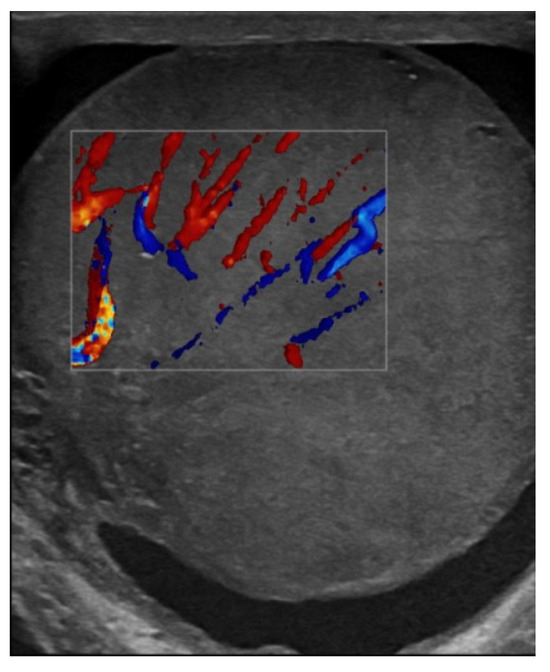

| June 2022 | first extramedullary relapse left testicular—diagnostic immunophenotyping of semen | HyperCVAD Block A radiotherapy, 24 gy/12 sessions for the scrotal sac and the lymph nodes along the left spermatic vein result: complete metabolic remission petct |